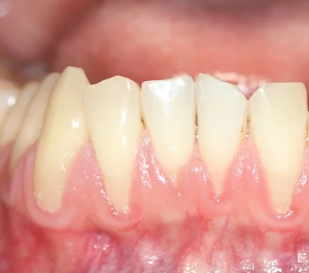

4. 잇몸이 내려가고 치아가 길어 보인다 – 잇몸 퇴축 현상

잇몸뼈가 녹아내리면, 잇몸이 치아뿌리 쪽으로 물러나면서 치아가 길어 보이는 현상이 나타납니다.

- 거울로 보면 치아가 평소보다 길게 보임

- 잇몸 경계가 울퉁불퉁하고 균일하지 않음

- 찬물 마실 때 시림이 심해짐

▶ 치아가 길어지는 건 단순한 미용 문제가 아닌 치아지지 구조 약화의 증거입니다.

7. 음식물이 자주 끼고, 잇몸 사이 공간이 벌어진다

잇몸이 내려가면서 치아 사이의 삼각형 틈(치간공간)이 넓어지고,

거기에 음식물이 자주 끼면 2차 세균 번식이 빠르게 일어납니다.